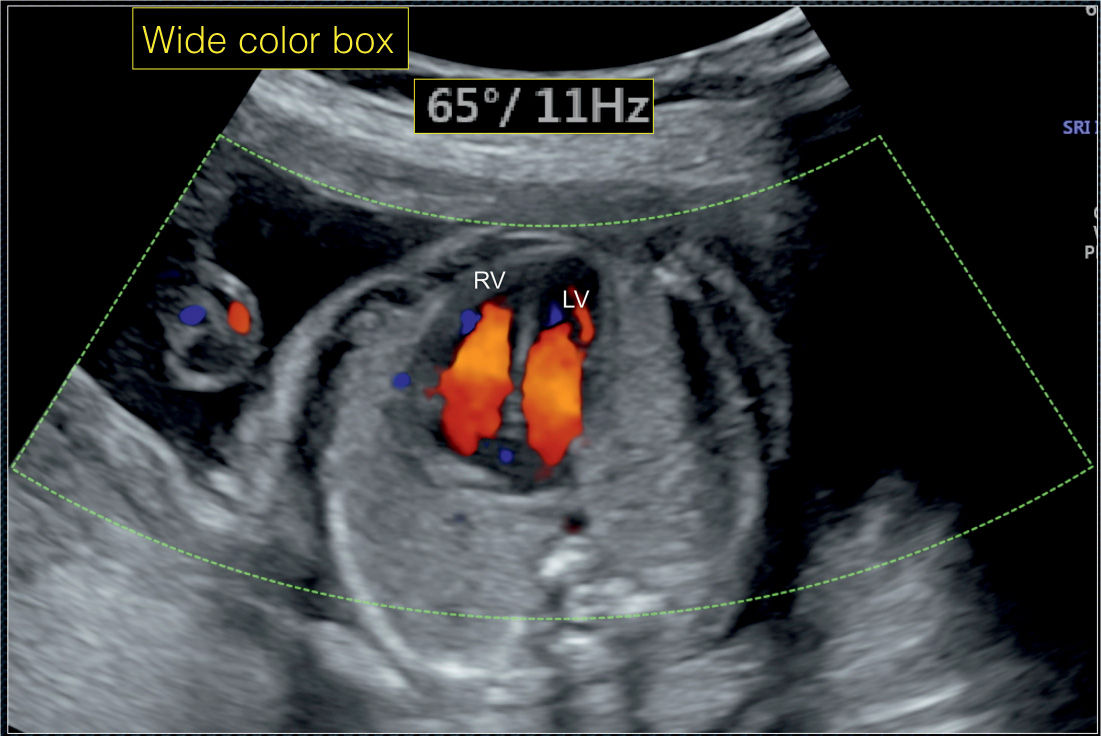

From obgynkey.com

Color Doppler in Fetal Echocardiography Obgyn Key How Is An Echo Done On A Fetus Learn about why it is done, and how. How is a fetal echocardiogram done? Fetal echo can help find heart defects before birth. Learn about the causes, symptoms, and treatment options for this. If a heart problem can be found early, the more likely. In conjunction with the bc women's hospital, fetal echocardiograms (ultrasound) are done to assess fetal heart. How Is An Echo Done On A Fetus.

Color Doppler in Fetal Echocardiography Obgyn Key How Is An Echo Done On A Fetus The test is typically performed by a specially trained ultrasound sonographer, and the images are interpreted by a pediatric cardiologist who. Learn about why it is done, and how. Fetal echo can help find heart defects before birth. Fetal echocardiography (echo) uses sound waves to check the heart of your developing baby. Fetal echocardiography (echo) uses sound waves to check. How Is An Echo Done On A Fetus.